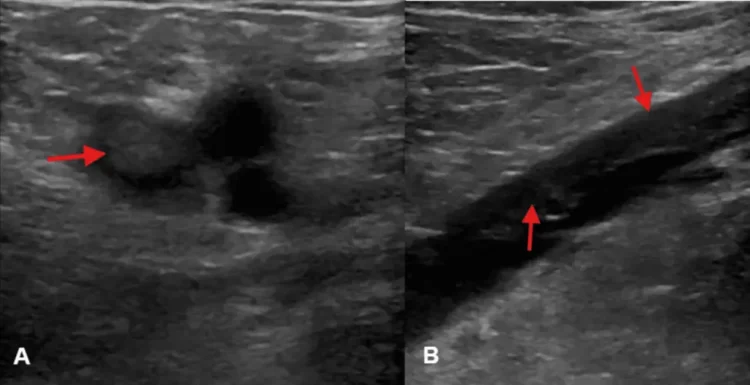

In addition to the news regarding O’Hara, a medical article published in Cureus detailing a case of rapid resolution of pulmonary embolism through a low-dose systemic thrombolytic infusion has also contributed to the increased searches. This article highlights innovative treatment options for the condition, further piquing the curiosity of those who may be researching the topic in light of recent events.